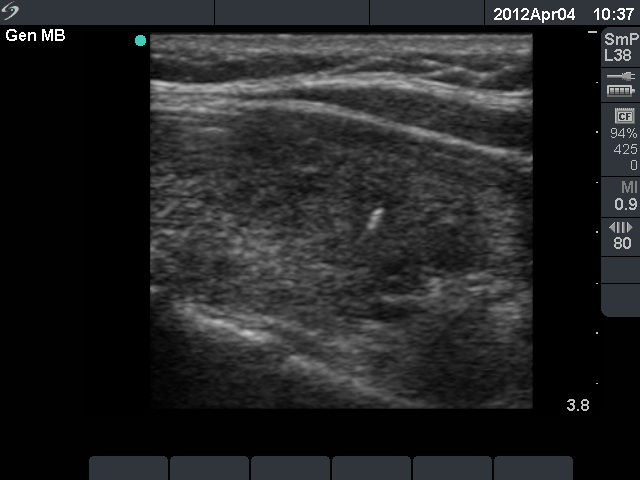

Third session of therapy (second row of images)

At this time we gave 1.5 mL ethanol.